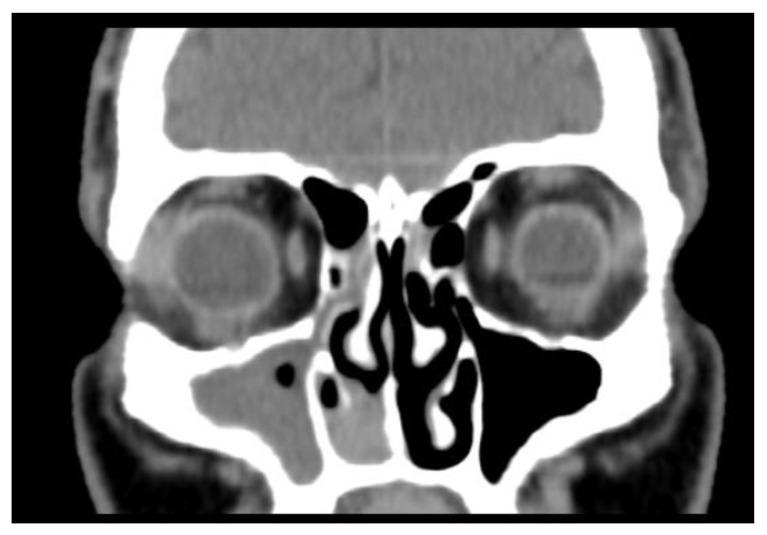

Developing in a limited space, rare tumors located at the nose and paranasal sinuses are sometimes difficult to diagnose due to their modest clinical presentation, which is uncorrelated with anatomopathological diversity. This limits the preoperative diagnosis without added immune histochemical study; for that reason, we present our experience with these tumors with the intention of raising awareness. The patient included in our study was investigated by our department through clinical and endoscopic examination, imaging investigations, and an anatomic-pathological study. The selected patient gave consent for participation and inclusion in this research study in compliance with the 1964 Declaration of Helsinki.

在有限的空间中发育,由于其临床表现温和,与解剖病理学多样性无关,位于鼻腔和鼻旁窦的罕见肿瘤有时难以诊断。这限制了没有额外免疫组织化学研究的术前诊断;因此,我们介绍了我们在这些肿瘤方面的经验,旨在提高认识。我们科室通过临床和内镜检查、影像学检查以及解剖病理学研究对纳入研究的患者进行了调查。所选患者同意参与并符合 1964 年赫尔辛基宣言纳入本研究。